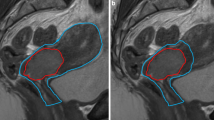

For GTV, the gross tumor volume and pathologic lymph nodes were delineated. For CTV the mesorectum, presacral space, internal iliac lymph node regions and, when applicable, obturator lymph node regions, were delineated by a radiation oncologist according to the guidelines by Roels et al. [21] (Advantage SIM, GE or VelocityAI 3.2, Varian Medical Systems). To be able to differentiate margins between the upper and lower mesorectum based on the geometrical uncertainties reported by Nijkamp et al [3, 4, 6], the mesorectum was divided into an upper and lower part, with the transition at the base of the bladder (Fig. 1). Total CTV volume was created by combining all CTV regions. Radiation therapists (RTTs) contoured the OARs (i.e., the bladder, bowel bag and femur heads) according to RTOG guidelines [22].

Margin sets based on anatomy as captured on planning CT. a shows an empty rectum with a set of 25 mm, 15 mm, and 0 mm margins (red) for the upper mesorectum (blue). b shows a full rectum with a set of 15 mm, 0 mm, and − 15 mm anterior margins (red) for the upper mesorectum (blue). Yellow is the lower mesorectum

Planning CT and delineations were imported into the treatment-planning system (Oncentra 4.5, Elekta AB, Sweden). PTV margins were created (VelocityAI) by expanding the lymph-node regions by 8 mm and the presacral space by 10 mm. The upper and lower mesorectum were expanded in all directions by 10 mm, except for the anterior side. The anterior side of the lower mesorectum was expanded by 15 mm. The anterior margin to the upper mesorectum was variable. To simplify the plan-selection process, we chose 15 mm as the difference between the PTV margins, except for the largest PTV margin, for which – on the basis of the maximum uncertainty found by Nijkamp – we chose 25 mm.

To reduce the number of PTVs in order to minimize workload at treatment planning, two sets of margins were defined, according to the anatomy captured on the planning CT scan: If a rectum was deemed empty after visual inspection on planning CT we used PTV margins of 25 mm, 15 mm, 0 mm, as − 15 mm was unlikely to be needed. Conversely, if a rectum was deemed full after visual inspection on planning CT, we used 15 mm, 0 mm and − 15 mm, as 25 mm was unlikely to be needed. Per patient, this resulted in 3 PTV margins, and thus 3 plans from which we could select during treatment (Fig. 1).